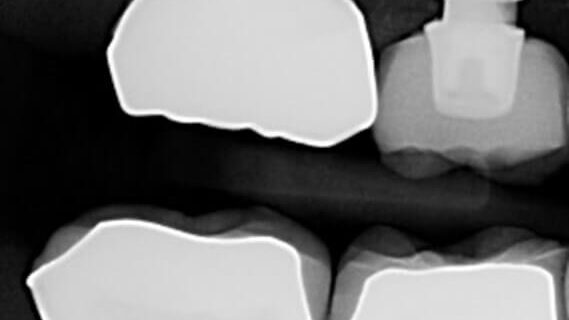

The case involves a failed abutment screw in a Nobel trilobe 4.3 implant in the #3 site.